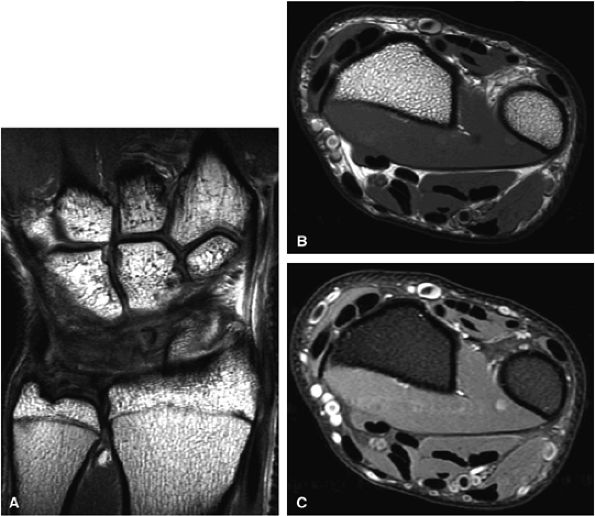

![]() |

|

FIGURE 1.18 ● Spin-echo, 8 echoes (10 to 80 msec). Note the signal attenuation in the patellar cartilage. This type of sequence is used to produce cartilage T2 color maps.

FIGURE 1.19 ● Color map (A) showing T2 values from 20 msec in red to 75 msec in blue, with calculated T2 values from the region of interest (ROI). ROI #1 green curve (B) shows the 8-echo signal pattern, and the red curve shows the calculated monoexponential fit.

FIGURE 1.20 ● Clinical examples of T2 mapping at 3 T. Color map showing T2 values from 25 msec in red to 75 msec in blue. (A, B) Osteoarthritis (arrow) is not visible on the conventional T2 image (A). (C, D) Autologous osteochondral implant (mosaicplasty) of the medial femoral condyle with mild prolongation of T2 values. (Courtesy H.G. Potter, HSS, NY)